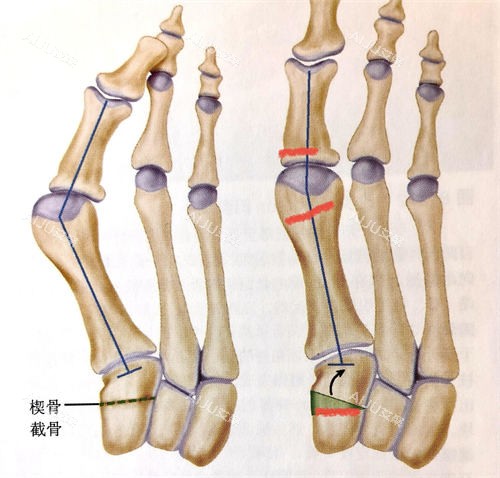

技术认证:掌握小创口拇外翻矫正、传统截骨术等多种术式,能根据患者脚型灵活调整;

中重度拇外翻:精密截骨+关节复位,解决骨头变形问题;